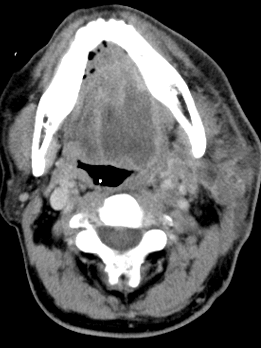

▲图为舌癌并左颈部肿物的纳米刀消融(颈外动脉位于肿物底部,无法分离)。

其中左图显示术中舌体立即变白;右图为术后10天,左侧舌部病灶周围组织大片水肿改变,邻近局部皮肤亦增厚粘连。